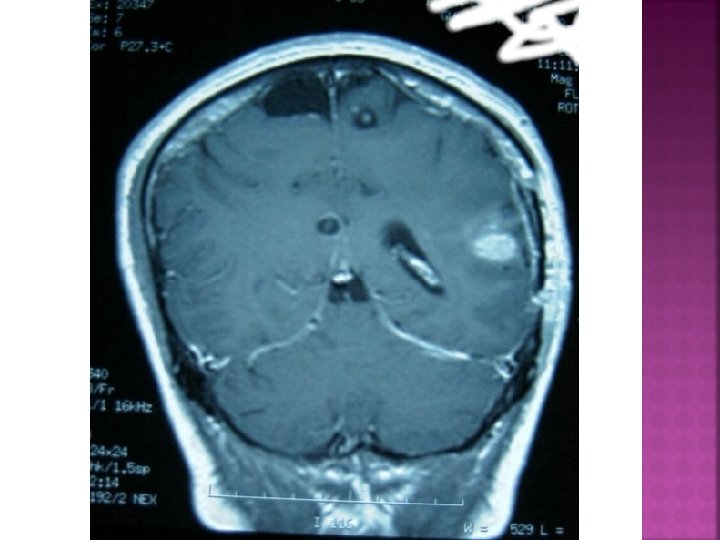

• ASCARIS • TRICOCEFALOS • UNCINARIOS • ESTRONGILOIDIS • AMEBAS • GIARDIA LAMBIA • TRICOMONIASIS • MIGRACIÓN LARVARIA CUTÁNEA • NEUROCISTICERCOSIS • ABSCESO HEPATICO AMEBIANO • MALARIA • PEDICULOSIS • TOXOPLASMOSIS

TENIA SOLIUM Y TENIA SAGINATA

TRATAMIENTO: PRAZIQUANTEL: CISTICID Tab 600 mgrs EFECTOS ADVERSOS: CEFALEA, MAREO, VÓMITO, CONVULSIONES.

PRAZIQUANTEL: Tab 600 mgrs